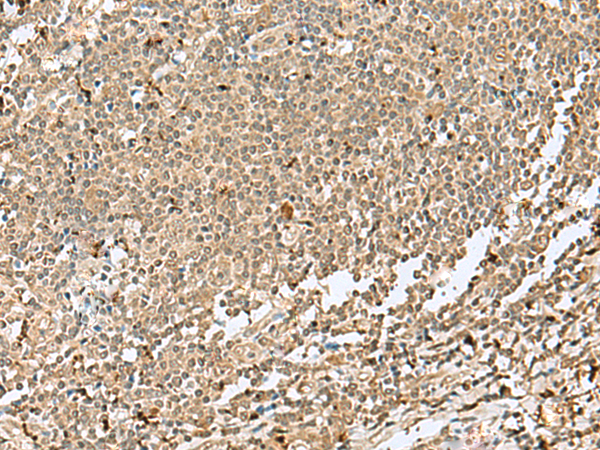

分类: 科研抗体货号: P09887别名: ZNF47; ZSCAN15应用: IHC反应种属: Human